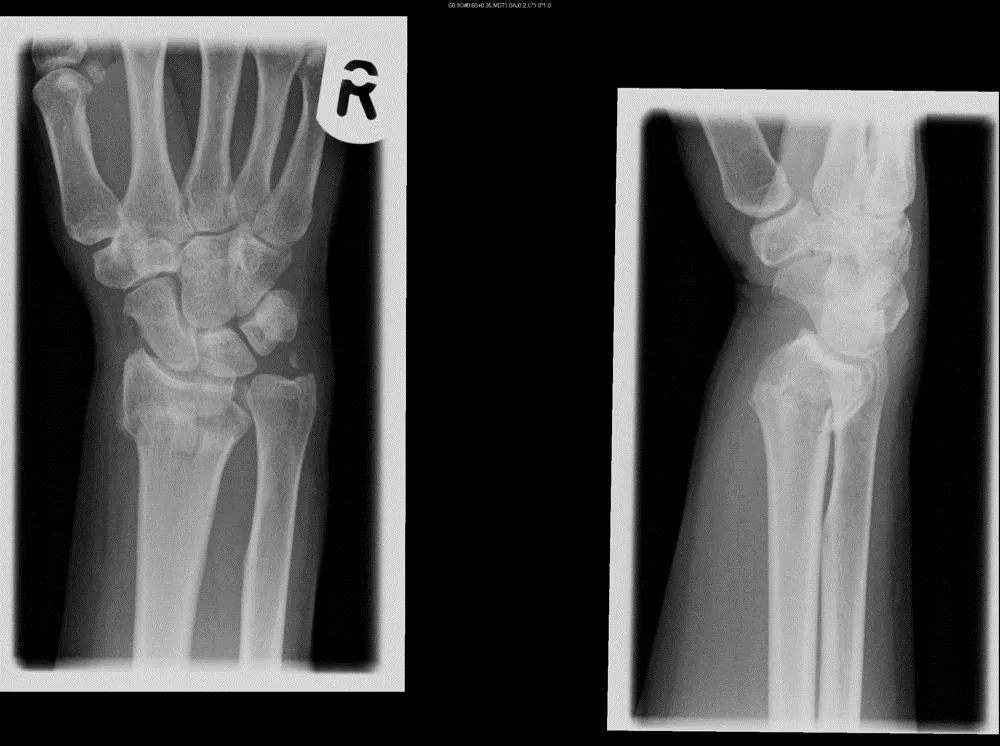

Изображения повреждения костей